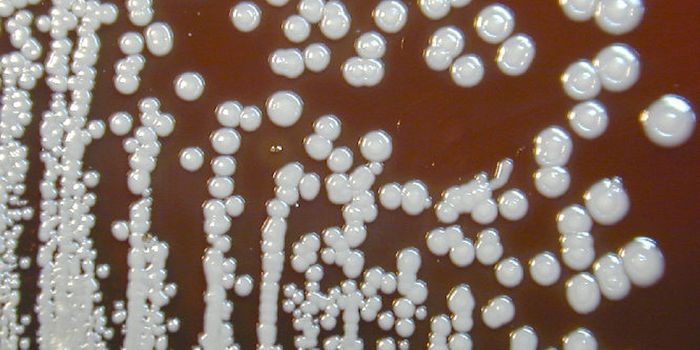

DEC 26, 2021Genetics & GenomicsCandida auris emerged as a pathogen around 2009, and has quickly become a serious problem for clinics and hospitals, whe ...

JUN 29, 2021MicrobiologyViruses are not the only microbes that can cause serious public health problems. Researchers have been warning about a p ...

JUN 21, 2021MicrobiologyIn Brazil, clinicians have noted a rise in C. auris infections. Researchers believe that exhausted healthcare workers, o ...